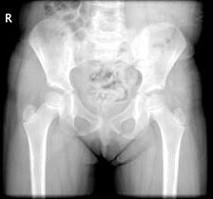

女,请根据其正常骨盆影像图像,判断其最可能的年龄 ( )A、11岁左右B、14岁左右C、5岁左右D、8岁左右E、2岁左右

问题 女,请根据其正常骨盆影像图像,判断其最可能的年龄 ( )

选项 A、11岁左右 B、14岁左右 C、5岁左右 D、8岁左右 E、2岁左右

答案 C